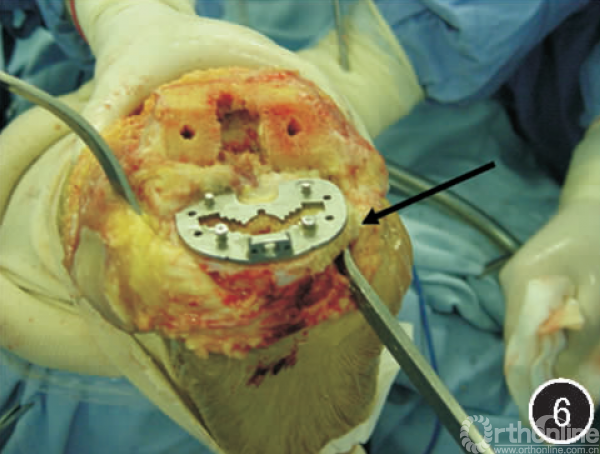

因此,正确的做法是胫骨平台假体必须要放置在白线之内,否则就要旋转错位。如果我们不将胫骨平台假体放置在白线之内,那就会使胫骨平台假体旋前,进而造成股骨与胫骨的受力点向胫骨平台后方转移,产生胫骨平台后方的应力集中,长期应力集中而造成胫骨平台聚乙烯垫的磨损和破坏。正确的手术操作应该是:把胫骨平台假体放到白线内之后,切除假体没有覆盖的骨赘,这样既矫正了旋转畸形,又能松解膝关节内侧副韧带的紧张(见图6)。

图6切除赘骨后,旋转畸形得到矫正,而且内侧副韧带也得到松解